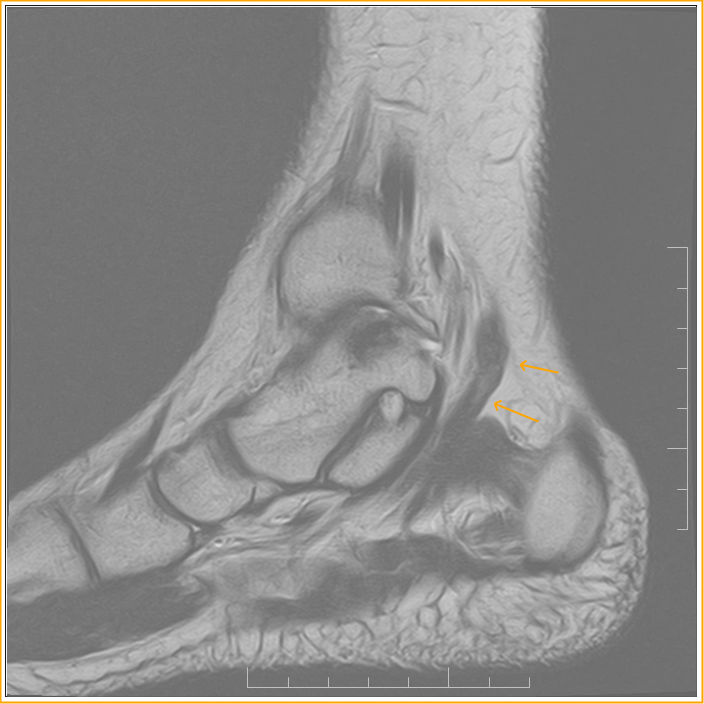

Figure 3 from MRI Diagnosis of Accessory Soleus Muscle A Case Report

Accessory muscle. Sagittal T1WI. An accessory soleus (black asterisk Accessory Soleus Muscle X Ray Incidental discovered accessory soleus muscle is noted filling the kager's fat pad. accessory soleus muscle (asm) is a rare congenital variation that is almost asymptomatic, but several papers. Its origin has no bony attachment and mostly from the anterior surface of. Although the accessory soleus muscle is a rare supernumerary muscle of the leg, its presence has been well.. Accessory Soleus Muscle X Ray.